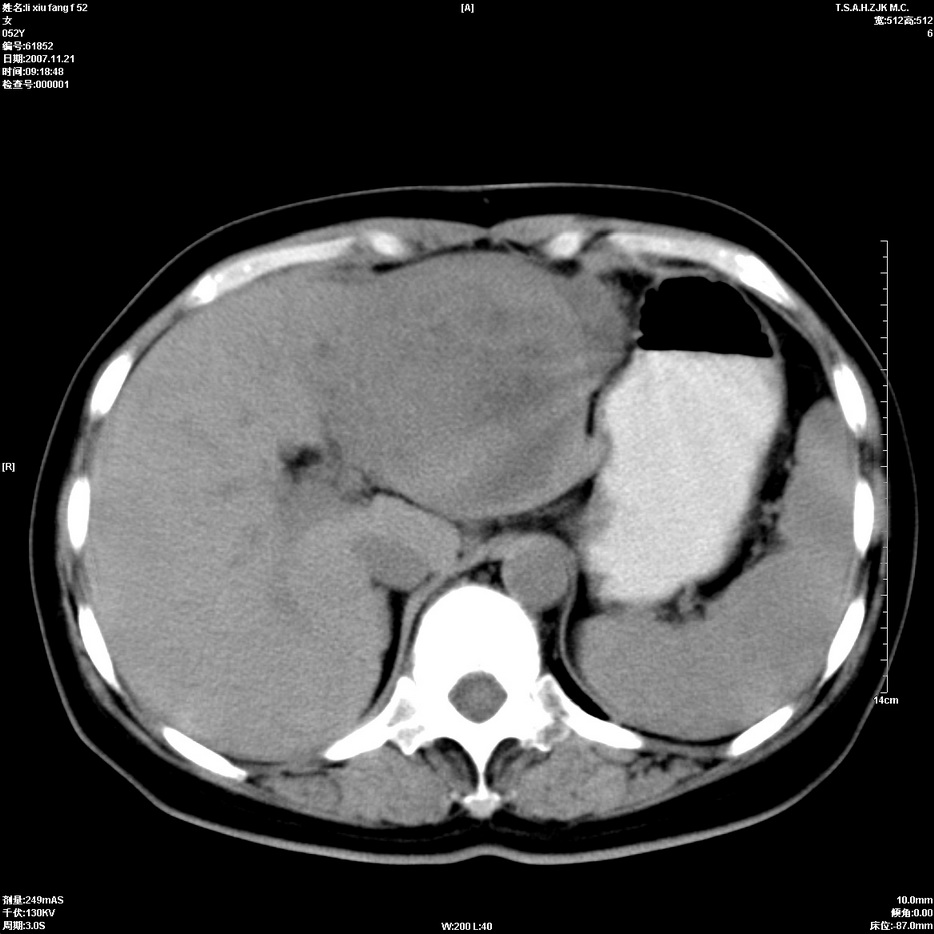

标题: CT12858:女,52岁,胎甲球蛋白861肝左叶占位,肝癌。下腔静 [打印本页]

标题: CT12858:女,52岁,胎甲球蛋白861肝左叶占位,肝癌。下腔静

肝左叶巨大低密度灶肿块,增强符合快进快出表现,有动静脉交通支;静脉期,下腔静脉内有充盈缺损,afp明显升高,支持肝癌并下腔静脉癌栓形成。

以下是引用拾荒者在2008-4-15 22:57:00的发言:[br]肝左叶巨大低密度灶肿块,增强符合快进快出表现,有动静脉交通支;静脉期,下腔静脉内有充盈缺损,afp明显升高,支持肝癌并下腔静脉癌栓形成。